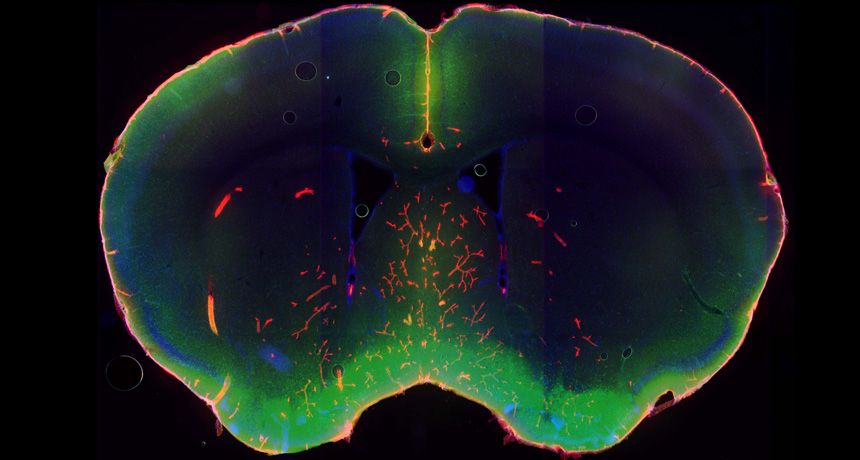

Исследователи из медицинского центра Рочестера в Нью-Йорке обнаружили очищающую функцию сна во время изучения того, как

В случае же если система отвода отходов забита, мусор от трудолюбивых нервных клеток начинают накапливаться. Ученые предполагают, что лишение сна или повреждение оросительной системы может привести к невозможности полноценной очистки